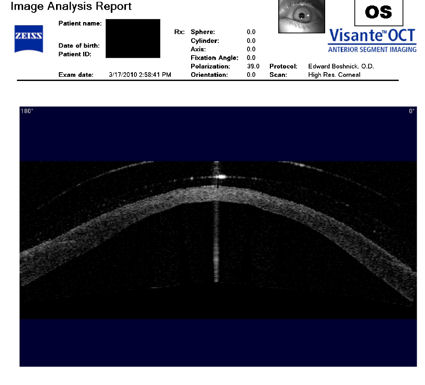

Следующие изображения были получены с использованием метода, называемого оптической когерентной томографией, или ОКТ. Прибор позволяет получить изображение в поперечном сечении путем сканирования передней части глаза (переднего сегмента) лучом света. Думайте об этом как об ультразвуке, использующем свет вместо звуковых волн для создания изображения живых тканей.

На изображении, приведенном непосредственно ниже, представлен снимок здоровой, неоперированной роговицы для сравнения со следующими изображениями эктатических роговиц после операции LASIK.

На изображении ниже представлен снимок роговицы в поперечном сечении после операции LASIK. Белая изогнутая линия вверху - это передняя поверхность твердой контактной линзы. Следующая едва заметная белая линия - это задняя поверхность линзы. Следующая область, которая имеет зернистый вид, - это пространство между хрусталиком и роговицей, заполненное физиологическим раствором. Роговица имеет классические признаки эктазии - истончение, выпуклость и неправильную форму.

Изображения любезно предоставлены доктором Эдвардом Бошником, который посвятил свою практику восстановлению качественного зрения и информации о эктазия после операции LASIK .